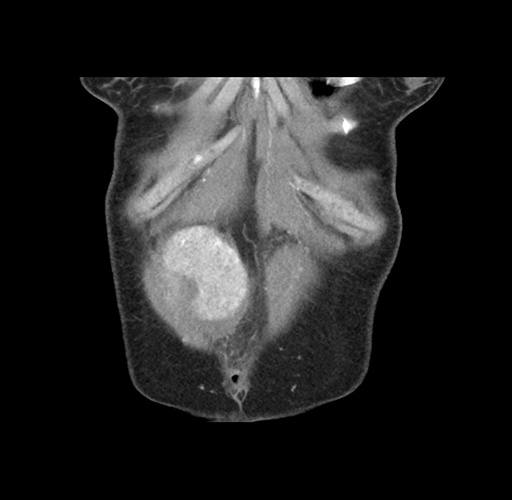

Imaging Analysis

Look through the patient's CT scan to identify any areas of concern for the necessary procedure.

Based on your CT findings, which issue(s) would give reason for "planned slowing down moment(s)" in this case?

Considering a standard left lateral sectionectomy procedure, what step(s) of the operation would you do differently in this case ?